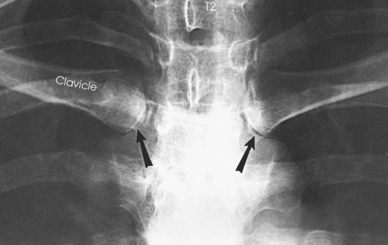

The number of ribs may be increased by the presence of cervical or lumbar ribs, or both. Cervical ribs articulate with the C7 vertebra but rarely attach to the sternum. Cervical ribs may be free or articulate or fuse with the first rib. Lumbar ribs are less common than cervical ribs. Lumbar ribs can lend confusion to images. They can confirm the identification of the vertebral level, or they can be erroneously interpreted as a fractured transverse process of the L1 vertebra.

Structures shown: A PA projection shows the sternoclavicular joints and the medial portions of the clavicles (Figs. 9-24 and 9-25).

Structures shown: A slightly oblique image of the sternoclavicular joint is shown (Figs. 9-28 and 9-29).